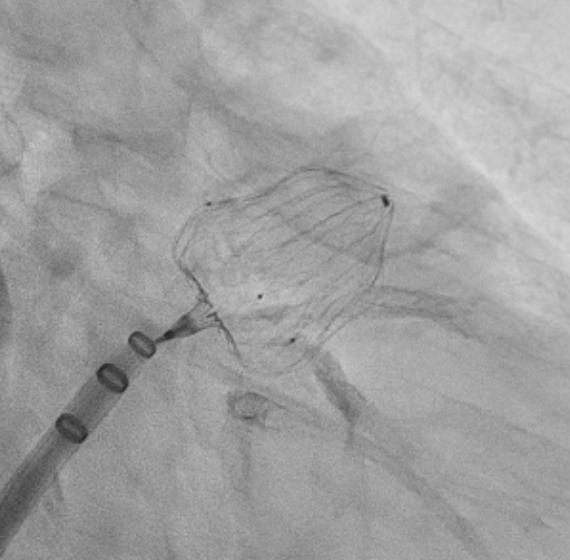

不整脈の一種である心房細動になると、心房が小刻みで不規則に拍動するため血液が淀み、内部で血栓(凝固した血液)が発生しやすくなります。心臓内で発生した血栓が脳の血管に流れていくと脳梗塞を発症してしまうため、心房細動の患者さまは抗凝固剤(血液を固まりにくくする薬)を服用することで脳梗塞を予防しているのですが、効果が薄い場合や逆に出血しやすくなってしまう場合もあり、より有用で効果的な治療法が模索されていました。

心房細動による血栓の約9割は左の心房にある左心耳というひだに発生することがわかっており、また左心耳は心臓の機能にとって影響のない場所であるため、その左心耳を物理的に閉鎖して血栓の発生を予防する手術が左心耳閉鎖術です。

WATCHMANは開胸することなく、患者様の足の付け根の静脈から挿入したカテーテルを通して左心耳に蓋をし、閉鎖するデバイスです。当院のCEはカテーテル室にて手技に使用する各種機器の準備、術中のデバイス出しなどを行っています。